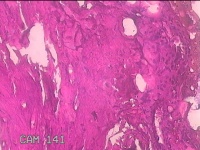

右侧耳垂结节

性别

男

年龄

24岁

临床诊断

耳垂新生物

一般病史

发现右侧耳垂结节3个月余。

标本名称

大体所见

灰白暗红色结节0.5x0.3x0.2cm一个,表面糜烂。

不具诊断价值。